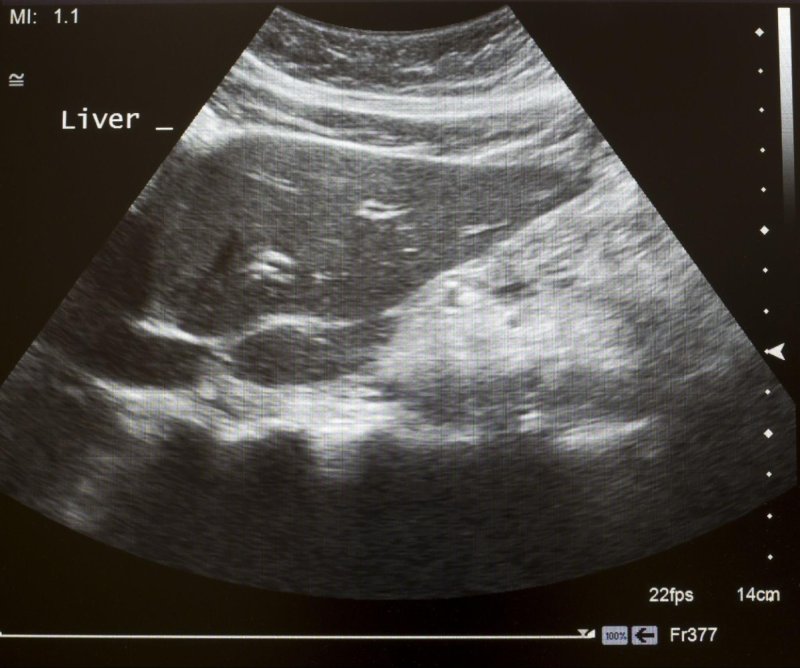

Siêu âm bụng khảo sát gan sử dụng sóng âm tần số cao tạo ra hình ảnh cấu trúc gan như thùy gan, phân thùy gan, hệ mạch máu gan. Từ đó, bác sĩ có thể phát hiện những tổn thương liên quan đến men cao gan như viêm gan, gan nhiễm mỡ, xơ gan, ung thư gan và có biện pháp can thiệp kịp thời. Quá trình thực hiện không xâm lấn, không đau, diễn ra khoảng 30 phút.